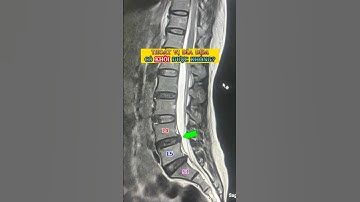

ĐỊNH VỊ TIM TRỤC, CHÂN CƠ CỘT.